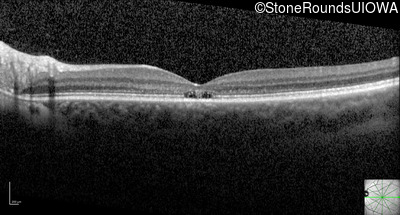

Optical Coherence Tomography - Left - 20/50 -2 sc

Exemplar / OCT Stack

OCT Stack